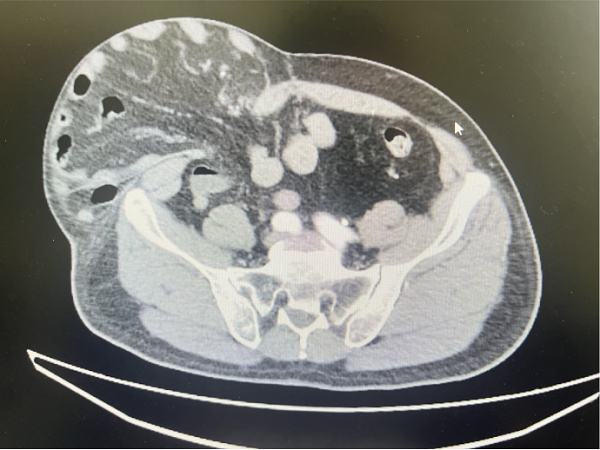

在丁晔副主任医师带领下,团队联合彭晴医师等医护人员,成功完成3台分属颈、胸、腰椎三大区域的高难度脊柱外科手术,病种涵盖退行性病变与创伤性骨折,融合微创内镜与经典开放技术,彰显科室综合诊疗实力。

3. 为胸椎爆裂性骨折患者施后路切开复位、微创减压内固定术(四级手术),胸椎爆裂性骨折常因高能量损伤导致,骨折块可能突入椎管压迫脊髓,致残风险高。丁晔副主任医师团队采用微创理念进行减压,并完成了有效的复位与坚强的内固定,既解除了对神经的压迫,又最大程度地减少了手术创伤,为患者争取了最佳的神经功能恢复条件。

三台手术均顺利完成,患者术后恢复良好,标志着我院脊柱疾病微创化、精准化治疗迈上新台阶。